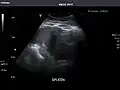

Spleen